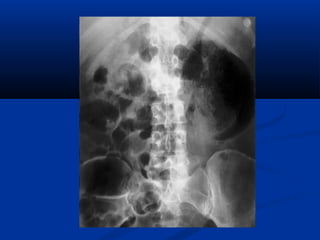

Lao niLao niệuệu

 Phân loại Elke :Phân loại Elke :

 Stade I : lao thận, X quang bình thườngStade I : lao thận, X quang bình thường

 Stade II : lao tạo hang (phá hủy < 1/3 thận)Stade II : lao tạo hang (phá hủy < 1/3 thận)

 Stade III : thận mủ > 1/3 thận (néphrectomie)Stade III : thận mủ > 1/3 thận (néphrectomie)

 UIV : khám nghiệm lựa chọn (vôi hoá, chít hẹp,UIV : khám nghiệm lựa chọn (vôi hoá, chít hẹp,

hình cộng..)hình cộng..)

Lao thaänLao thaän

Sieâu aâm:Sieâu aâm:

• **Thaän vaø nieäu quaûn:Thaän vaø nieäu quaûn:

• - Voâi hoaù trong thaän- Voâi hoaù trong thaän

• - Chít heïp = giaõn heä beå- Chít heïp = giaõn heä beå

ñaøiñaøi

• - Hình aûnh coäng: taïo- Hình aûnh coäng: taïo

hang, xoang tuûy…hang, xoang tuûy…

• - Thaän teo nhoû, voâi- Thaän teo nhoû, voâi

hoaùhoaù

• ** Baøng quang :Baøng quang : daøydaøy

vaùchvaùch

Öu theá UIV trong lao nieäuÖu theá UIV trong lao nieäu

SA giuùp ích höôùng daãnSA giuùp ích höôùng daãn

Rein Mastic

Calcifications surrénaliennes

Images d’addition

Hang lao và chít hẹp